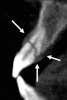

Figure 2a  Another case that clearly shows additional canal anatomy (distolingual root) not easily detected by periapical radiographs. Periapical radiograph depicting possible widened periodontal ligament (A). The CBCT clearly shows the missed canal in all three dimensions (B). The postoperative periapical radiograph shows the re-treatment, which includes the obturation of the distolingual canal24 (C).

Figure 2a

Figure 2b  Another case that clearly shows additional canal anatomy (distolingual root) not easily detected by periapical radiographs. Periapical radiograph depicting possible widened periodontal ligament (A). The CBCT clearly shows the missed canal in all three dimensions (B). The postoperative periapical radiograph shows the re-treatment, which includes the obturation of the distolingual canal24 (C).

Figure 2b

Figure 2c  Another case that clearly shows additional canal anatomy (distolingual root) not easily detected by periapical radiographs. Periapical radiograph depicting possible widened periodontal ligament (A). The CBCT clearly shows the missed canal in all three dimensions (B). The postoperative periapical radiograph shows the re-treatment, which includes the obturation of the distolingual canal24 (C).

Figure 2c

Initially, case studies appeared in the endodontic literature in which patients underwent CBCT imaging for the purposes of diagnosis20-22 and presurgical treatment planning.19 Recent reports have successfully shown the use of CBCT to locate missed canals,23 detect the extent of dentoalveolar fractures,20 identify resorption patterns,22 and compare cystic with granulomatous periapical lesions.17 Figure 2A through Figure 2C show a case in which the missed canal was suggested by periapical radiographs but confirmed with CBCT.24 Similarly in Figure 3A through Figure 3D, the additional diagnostic information attained from CBCT confirmed the diagnosis and extent of the root fracture, which initially was observed in the periapical radiographs (Figure 4A and Figure 4B).20 Notably, the extent of the lingual fracture as well as any alveolar complications could be visualized by CBCT only.